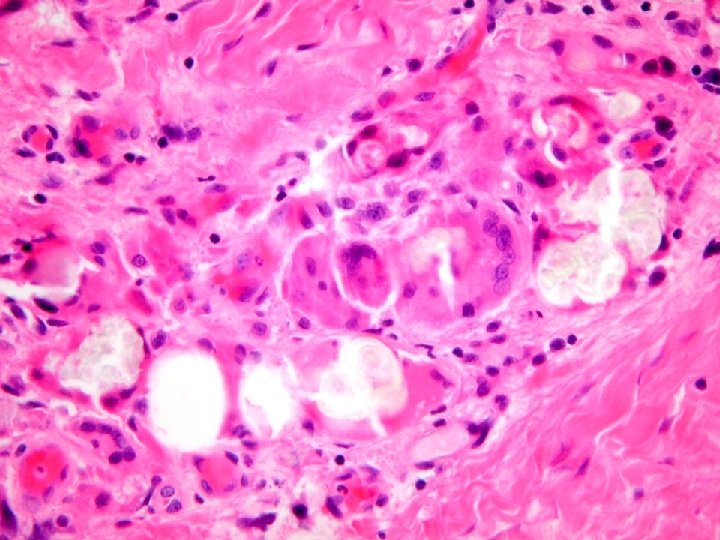

Diagnosis Renal Biopsy: • Acute bacterial interstitial nephritis with pus casts probably on the basis of partial ureteral obstruction by calcium oxalate debris. • Tubular deposition of calcific debris, both calcium phosphate and calcium oxalate. • Possible subclinical immune complex glomerulonephritis. • No evidence of rejection. • (G 0 CG 0 I 3 CI 2 T 1 CT 2 V- CV- AH 2 MM 0)

Diagnosis Renal Biopsy: Kidney allograft biopsy (10 months posttransplantation): Active chronic tubulointerstitial nephritis A) Changes consisted with chronic obstruction B) Banff Score G 0 CG 0 I 3 CI 2 T 2 CT 2 V 0 CV 0 AH 1 MM 0 C) No deposits by EM Proximal right ureter: A) Focal granulation tissue consistent with ischemic damage B) Granulomatous reaction to crystalline material, consistent with oxalate deposits

Diagnosis Renal Biopsy: • Chronic pyelonephritis with medullary calcium oxalate deposition related to systemic oxalosis • No evidence of rejection • Banff scores: – G 0 CG 1 I 1 CI 1 T 0 CT 1 V 0 CV 1 AH 0 MM 0